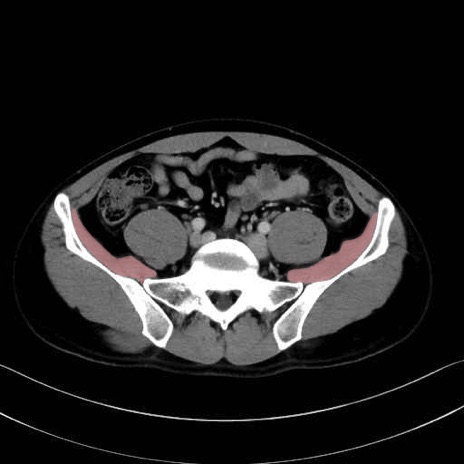

大腰筋 (Psoas major)

腸骨筋 (Iliacus)